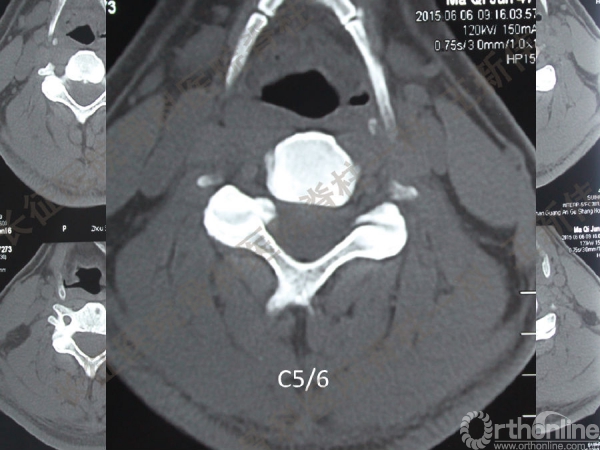

王新伟:颈椎后路通道下手术病例报告及文献回顾

颈椎后路通道下手术有哪些?颈椎后路通道下手术能做哪些事?颈椎后路通道下手术有哪些优势?长征医院骨科医院脊柱一科王新伟副教授通过临床病例报告及文献回顾,给出了他的答案——